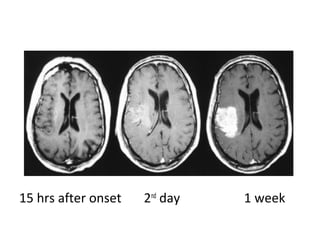

8 hrs after onset 2nd

day 1 week

6.5 hrs after onset 2nd

15 hrs after onset 2nd

23 hrs after onset 2nd